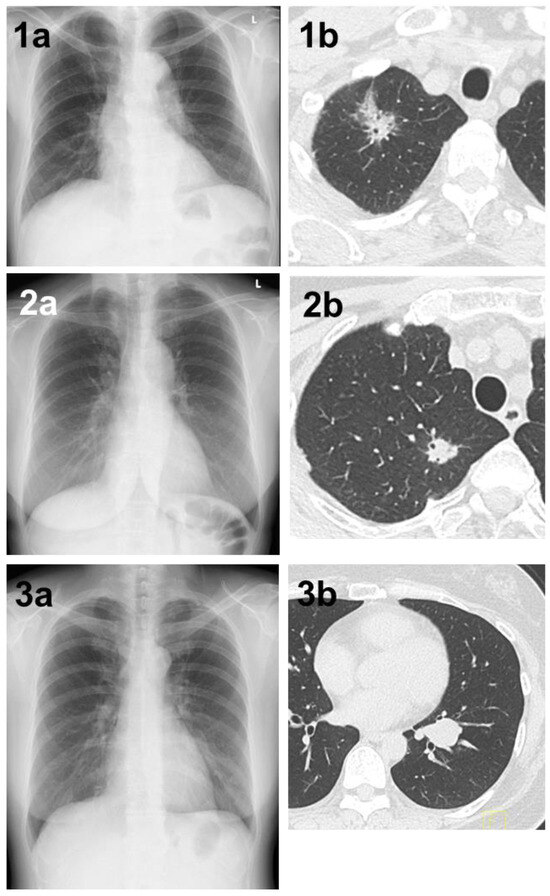

The main reasons why lung tumors could not be detected by the AI in 84 cases are listed in Table 2. Thirty-five cases had lesions overlapping with anatomical structures, such as the mediastinum, heart, and clavicle, or lesions below the diaphragm. Eight of these 35 cases were detectable by physicians (Figure 1). Conversely, there was one case in which it was difficult for physicians to detect the shadow overlapping the anatomical structures, but it was detected by AI (Figure 2). Eighteen cases were AIS, thirteen were lepidic adenocarcinoma (invasive size: 0.05–2.0 cm), and six were small nodules less than 0.7 cm in diameter. The other six cases were difficult to visualize on chest radiographs. Of these six cases, three cases had ground-glass components as the main component on CT, and one case had nodule and pulmonary vessels visible in succession. Many of these lesions were difficult to visualize due to the imaging conditions. Six patients did not fit these conditions; their lesions could be determined by physician interpretation, and their non-detection was judged to be an oversight by the AI (Figure 3).

Figure 1. (1a) A shadow overlapping the clavicle in the right upper lung field that could not be determined by AI. (1b) Chest CT showing a mass with a total size of 4.3 cm and a solid size of 2.1 cm in the right S1 region. The histopathological diagnosis was adenocarcinoma (lepidic adenocarcinoma), total tumor and invasive size of 1.7 cm, pT1bN1M0 (stage IIB). (2a) A shadow overlapping the clavicle in the right upper lung field that could not be pointed out by AI diagnosis. (2b) Chest CT showing a nodule with a total and solid size of 1.6 cm in the right S1 region. The histopathological diagnosis was adenocarcinoma (lepidic adenocarcinoma), tumor total and invasive size 1.7 cm, pT1bN1M0 (stage IIB). (3a) A shadow that could not be determined by AI despite being a large tumor of 4 cm in diameter. A shadow running parallel to the blood vessels, partially overlapping the heart shadow in the left lower lung field. (3b) Chest CT showing a mass with a total and solid size of 4.3 cm in the left S8–9 region. The histopathological diagnosis was adenoid cystic carcinoma, total tumor and invasive size of 4.0 cm, pT2aN0M0 (stage IB).